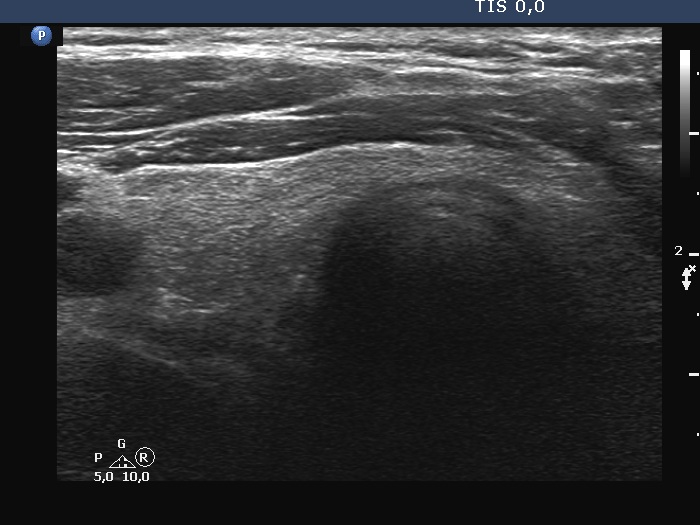

Initial examination (first row of images):

Clinical presentation: A 43-year-old man was referred for evaluation of neck complaints which have started 6 weeks ago when both sides of the neck became tender and occasionally painful. The patient noticed recurrent fever. Non-steroid anti-inflammatory drugs had only temporary effect.

Palpation: Both lobes were hard and painful on palpation.

Laboratory examination: TSH 0.02 mIU/L, FT4 28.7 pM/L, aTPO < 28 U/mL, CRP 55.7 mg/L

Ultrasonography: Both lobes had hypoechoic areas which showed ill-defined borders. The echogenicity index was around 50%. The hypoechoic areas were avascular.

Suggestion. Six-week steroid therapy.